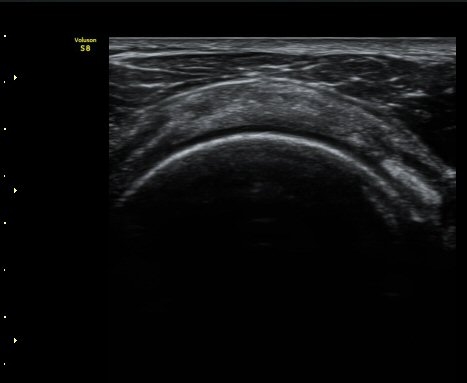

¾î±ú ¾Õ À̵ιڱ٠Ⱦ´Ü¸é°Ë»ç¿¡¼­ ÀÌºÎ¹Ú±Ù°Ç °í¶û ¾Æ·¡ ºÎÀ§¿¡¼­ À̵ιڱ٠ÀåµÎ ÁÖÀ§¿¡

¼ö¾×Àú·ù°¡ °üÂûµÈ´Ù(±×¸² 1, 2). °ß°©ÇÏ±Ù°Ç Á¾´Ü¸é°Ë»ç¿¡¼­ °ß°©ÇϱٰÇÀÇ °üÀý³»ºÎÀ§(±×¸² 3)